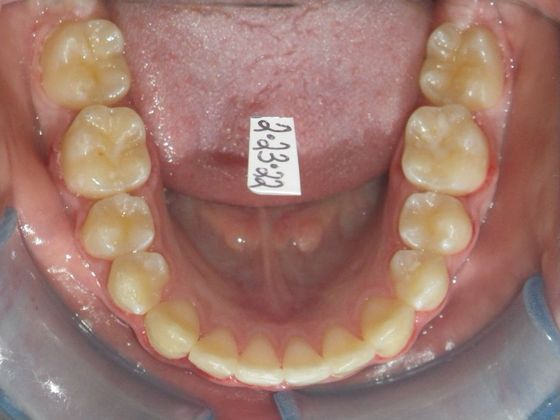

Orthodontics: Case 34

This patient had an upper right permanent cuspid that was impacted and would need uncovering by oral surgeon who would place bracket with chain to help enable us to tease the permanent cuspid into its proper position. She also had a permanent 2nd Molar that was impacted due to improper development of 3rd molars and the oral surgeon could remove them at the same time as uncovering of the permanent cuspid. After uncovering and removal of lower 3rd molars, we would begin comprehensive straight wire orthodontic treatment.